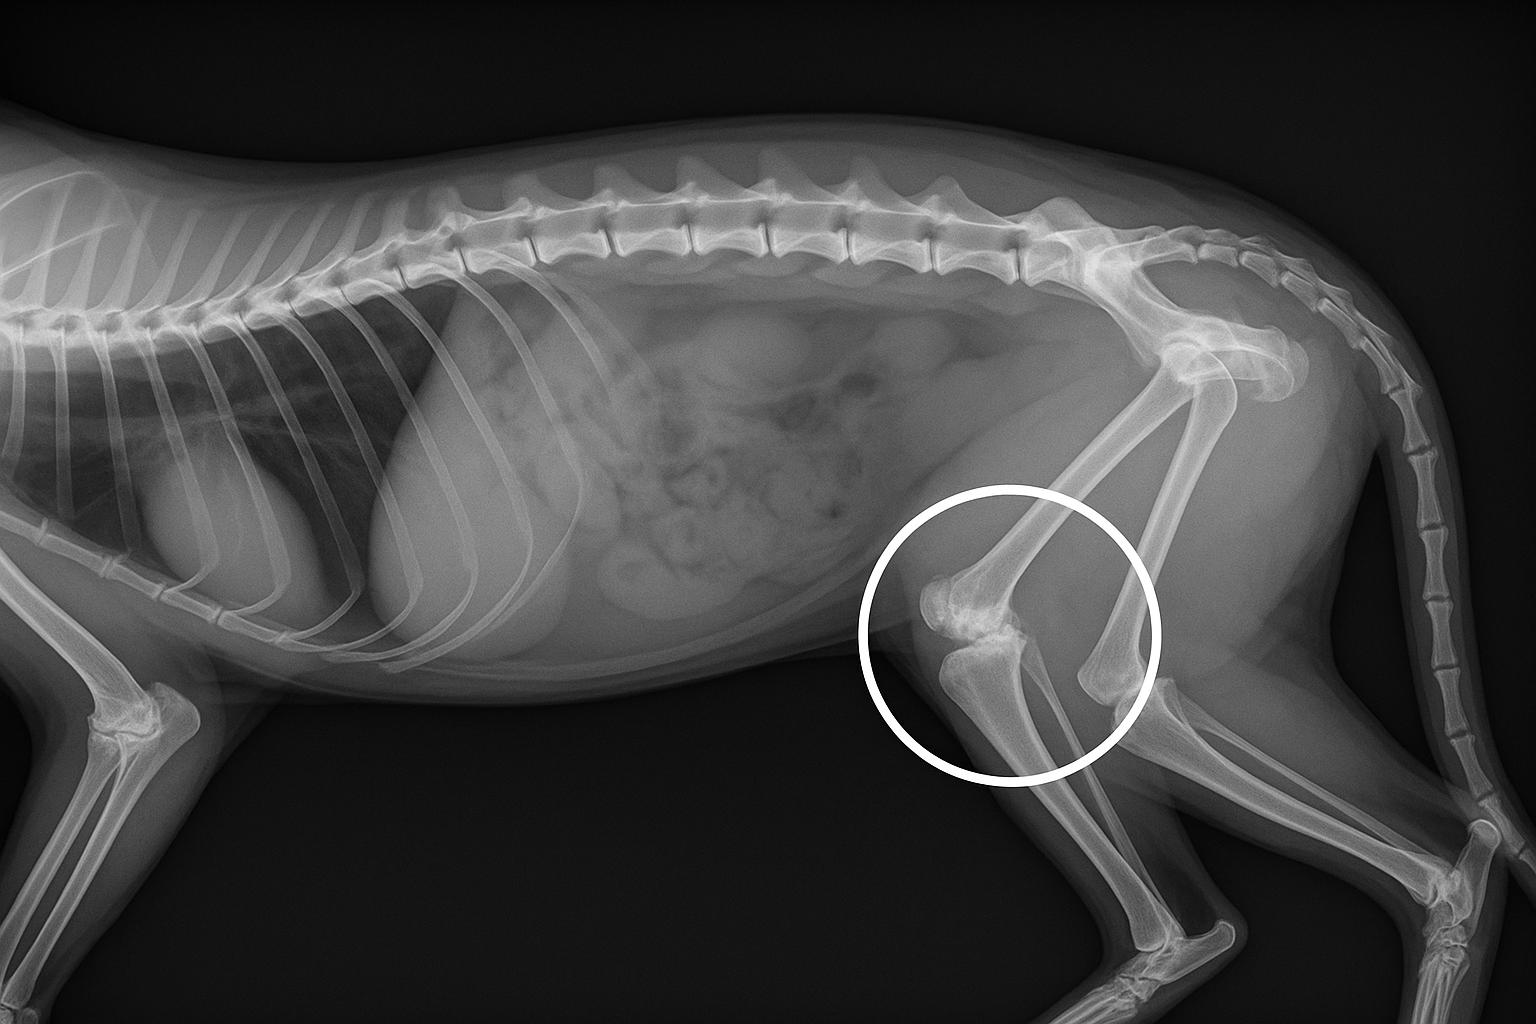

Si te preguntas: "¿cómo saber si mi gato tiene artritis?", debes saber que el diagnóstico en nuestros felinos requiere una combinación de varios pasos. Primero, una exploración física adecuada, en la que se palpan las articulaciones para detectar dolor, inflamación o rigidez. También es fundamental una anamnesis completa con el cuidador, en la que se consultan cambios en el comportamiento y estado físico del gato, entre otras preguntas. Finalmente, se realizan pruebas complementarias, como técnicas de diagnóstico por imagen, para confirmar el diagnóstico.

Entre estas pruebas, la radiografía es la técnica más común, ya que permite visualizar alteraciones en las articulaciones, como la formación de hueso nuevo u osteofitos, la reducción del espacio articular, erosiones óseas o el engrosamiento de la cápsula articular. En casos más complejos o dudosos, pueden requerirse técnicas avanzadas como la resonancia magnética o la tomografía computarizada, que permiten evaluar mejor los tejidos blandos y el cartílago.